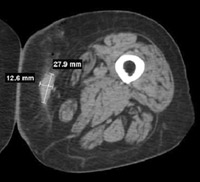

【投与前】

【投与後】

悪性黒色腫(メラノーマ)にテロメライシンを投与した例です。

これまたかなり分かりにくいんですが、若干、腫瘍が縮小しているのが分かるかと思います。

臨床評価が可能だった、9人中6人で腫瘍が6.6~35パーセント縮小したとのことです。